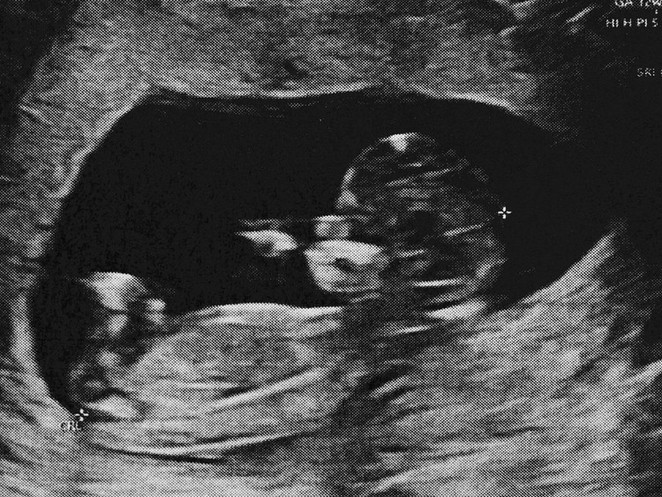

Roboter sollen künftig Babys austragen – doch es gibt Kritik